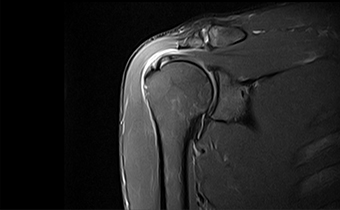

能在1秒内完成对任意部位,任意区域的快速精准匀场。磁场均匀度可达0.002ppm。在极速匀场过程中,几乎不受运动伪影的影响。

呈现大FOV、偏中心优质图像;实现大范围压脂成像,缩短压脂序列时间

改善脂肪抑制效果,减小DWI图像伪影。改善SWI等对B0涡流敏感序列的图像质量